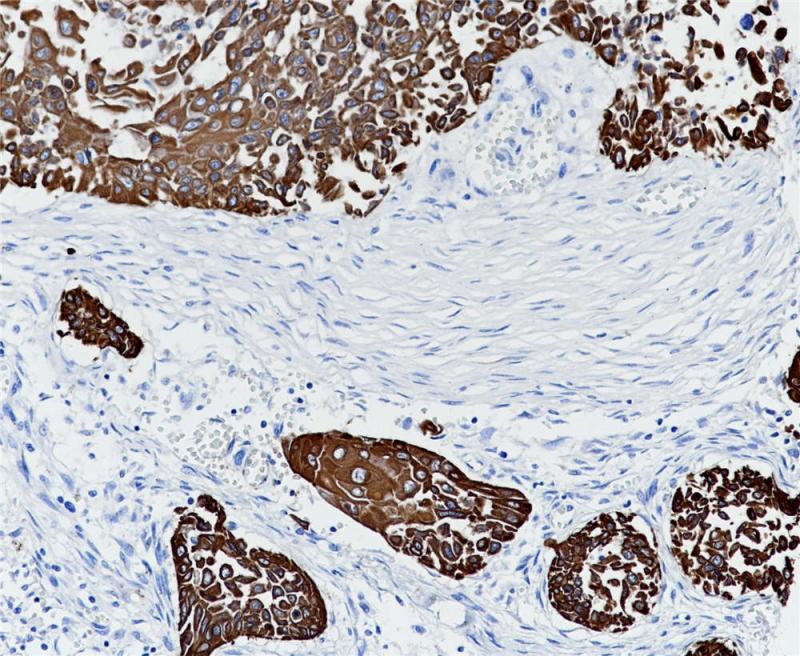

CK17在正常组织中主要表达于复层上皮和假复层上皮的基底细胞以及部分腺体(如唾液腺)的肌上皮细胞中。该抗体主要用于肺、子宫颈和口腔鳞状细胞癌的诊断。

阳性对照

食管癌